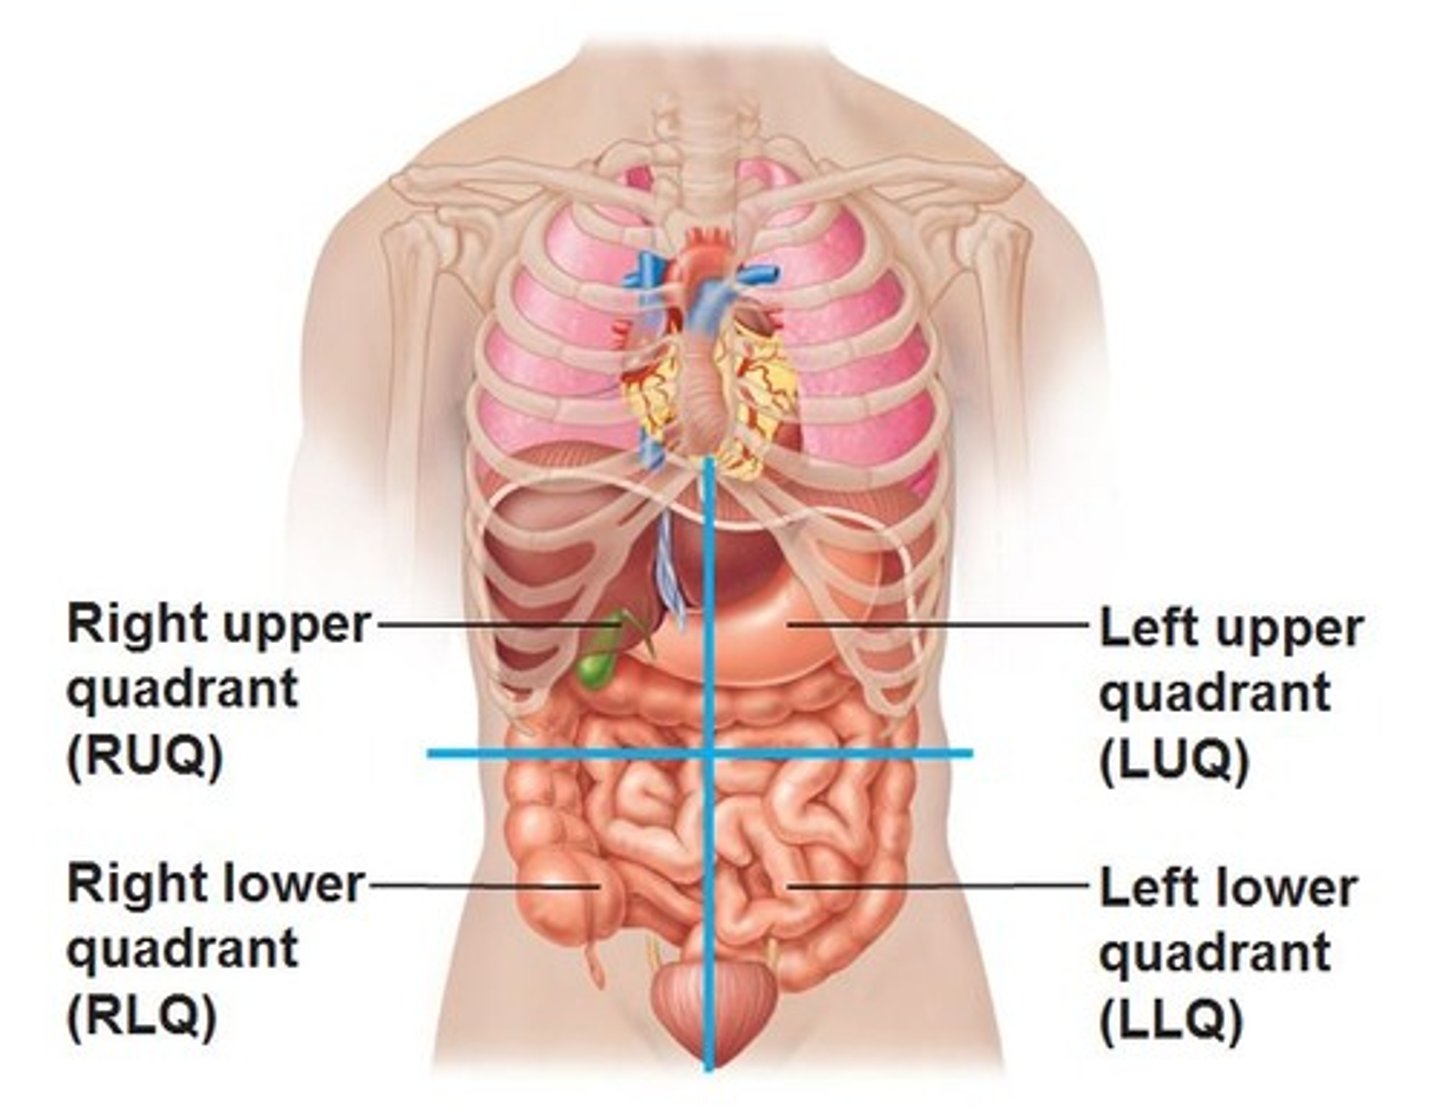

What are the 4 abdominal quadrants?

right upper quadrant, left upper quadrant, right lower quadrant, left lower quadrant and the diaphragm